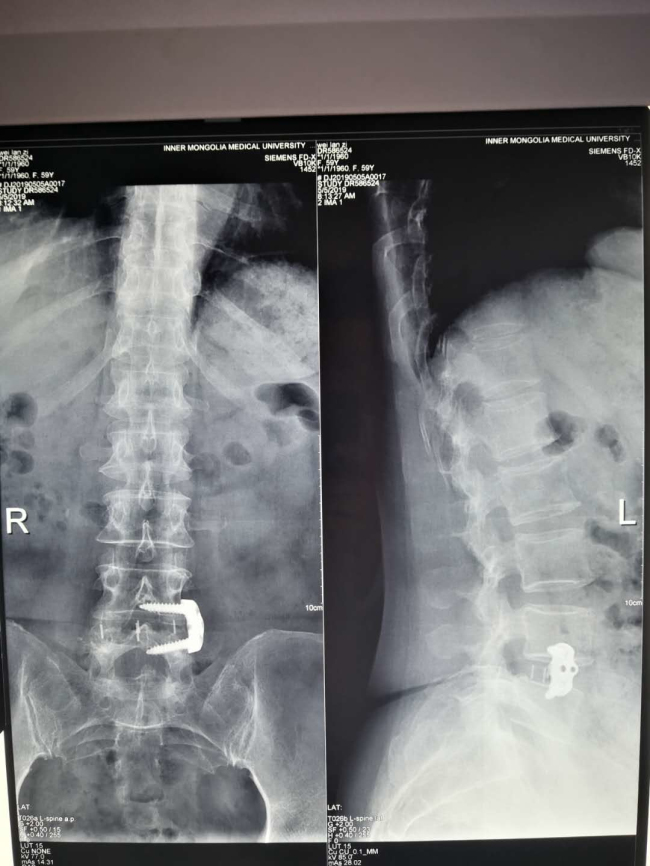

近日,91直播 微创脊柱外科成功为一名“腰椎不稳定继发腰椎管狭窄症”的59岁女性患者实施“OLIF”手术,为患者解除腰痛顽疾。

近年来,随着脊柱微创理念的更新以及微创技术不断发展,“靶点”治疗得到广大医学同道及患者的高度认可,常规脊柱手术逐步微创化、可视化、有限化及智能化。而OLIF(即斜外侧入路椎体间融合内固定术)治疗腰椎不稳定正是其中之代表。此项技术仅使用于腰椎不稳定伴或不伴轻度椎管狭窄,以及椎间盘源性痛的患者。此例手术皮肤切口约4cm,经腹膜外、腰大肌前缘入路,术中出血量仅为25mL。因其术中出血少,不干扰椎管内结构,对腰大肌及腰背肌无影响,无需引流,术后72小时即可下地活动,并发症发生率低,术后恢复快,住院时间短,治疗费用低,患者易于接受。